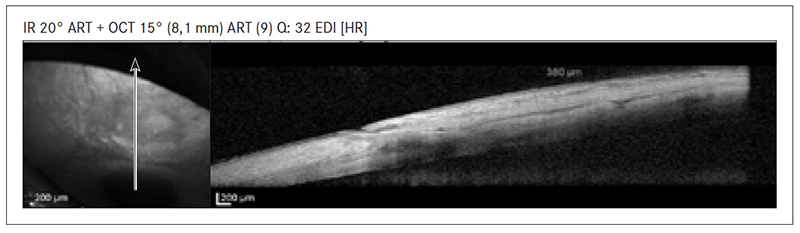

- plakans filtrācijas spilventiņš – subkonjunktivālas telpas neesamība, ciešs kontakts starp sklerālo gultni un spilventiņa sieniņu (sk. 4. att.).

4. attēls. Plakans filtrācijas spilventiņš / Flattened filtration bleb